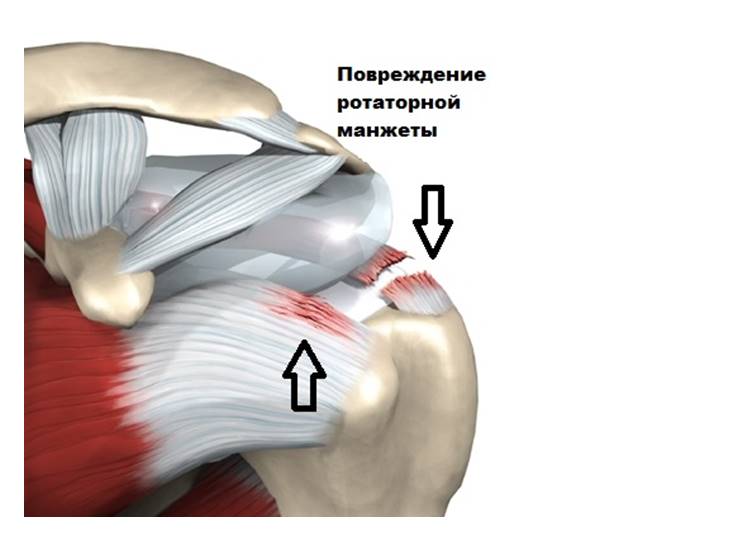

Фотографии мышц ротаторной манжеты плеча